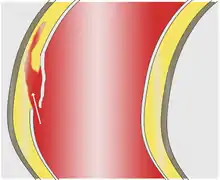

Blood penetrates the intima and enters the media layer.

As with all other arteries, the aorta is made up of three layers, the intima, the media, and the adventitia. The intima is in direct contact with the blood inside the vessel, and mainly consists of a layer of endothelial cells on a basement membrane; the media contains connective and muscle tissue, and the vessel is protected on the outside by the adventitia, comprising connective tissue.[25]

In an aortic dissection, blood penetrates the intima and enters the media layer. The high pressure rips the tissue of the media apart along the laminated plane splitting the inner two-thirds and the outer one-third of the media apart.[26] This can propagate along the length of the aorta for a variable distance forward or backward. Dissections that propagate towards the iliac bifurcation (with the flow of blood) are called anterograde dissections and those that propagate towards the aortic root (opposite of the flow of blood) are called retrograde dissections. The initial tear is usually within 100 mm of the aortic valve, so a retrograde dissection can easily compromise the pericardium leading to a hemopericardium. Anterograde dissections may propagate all the way to the iliac bifurcation of the aorta, rupture the aortic wall, or recanalize into the intravascular lumen leading to a double-barrel aorta. The double-barrel aorta relieves the pressure of blood flow and reduces the risk of rupture. Rupture leads to hemorrhaging into a body cavity, and prognosis depends on the area of rupture. Retroperitoneal and pericardial ruptures are both possible.[27]

The initiating event in aortic dissection is a tear in the intimal lining of the aorta. Due to the high pressures in the aorta, blood enters the media at the point of the tear. The force of the blood entering the media causes the tear to extend. It may extend proximally (closer to the heart) or distally (away from the heart) or both. The blood travels through the media, creating a false lumen (the true lumen is the normal conduit of blood in the aorta). Separating the false lumen from the true lumen is a layer of intimal tissue known as the intimal flap.